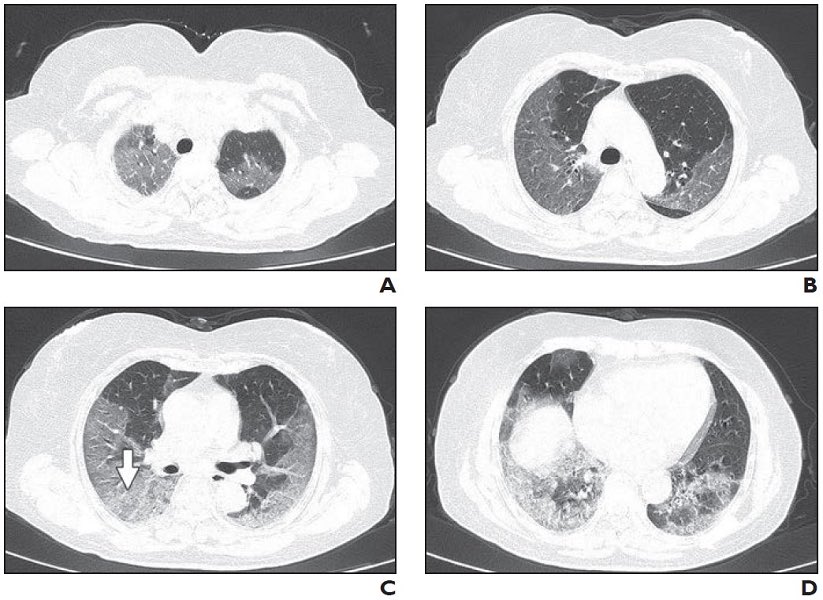

ويبدأ الضغط على الرئتين وذلك لكونها أصبحت ساحة المعركة الرئيسية، حيث ستنتفخ بالخلايا المناعية، والجزيئات والسوائل التي تستخدمها للتنقل وستقوم الخلية التائية القاتلة بالبحث عن الفيروس لتلتصق به وتقوم بقتله فورا، وتبدأ خلايا الدم البيضاء بابتلاع كمية كبيرة من جزئيات الفيروس الميته

وقد تتراكم هذه الخلايا على الرئتين ، ووجود هذه الخلايا على الرئتين سيسد مجاري الهواء وتقلل تدفق الأوكسجين .. وبالتالي سيسبب ضرر قوي على الشخص المصاب ، وسيمنعه من اخذ الاوكسجين الكافي ، وبالتالي سيحتاج الى أجهزة تنفس صناعية .. بعض الحالات تتأثر بشدة !

الأحداث السابقة سيكون عليها ضرر على الرئتين .. حيث هناك حالات حرجة سيعانون من ضرر دائم وقد تكون من ضمن من يعانون من أمراض مزمنة ، وحالات ستتعافى ولن يكون لديها سواء أنها عانت من إصابة سابقة من فايروس (كوفيد 19 / كورونا) !